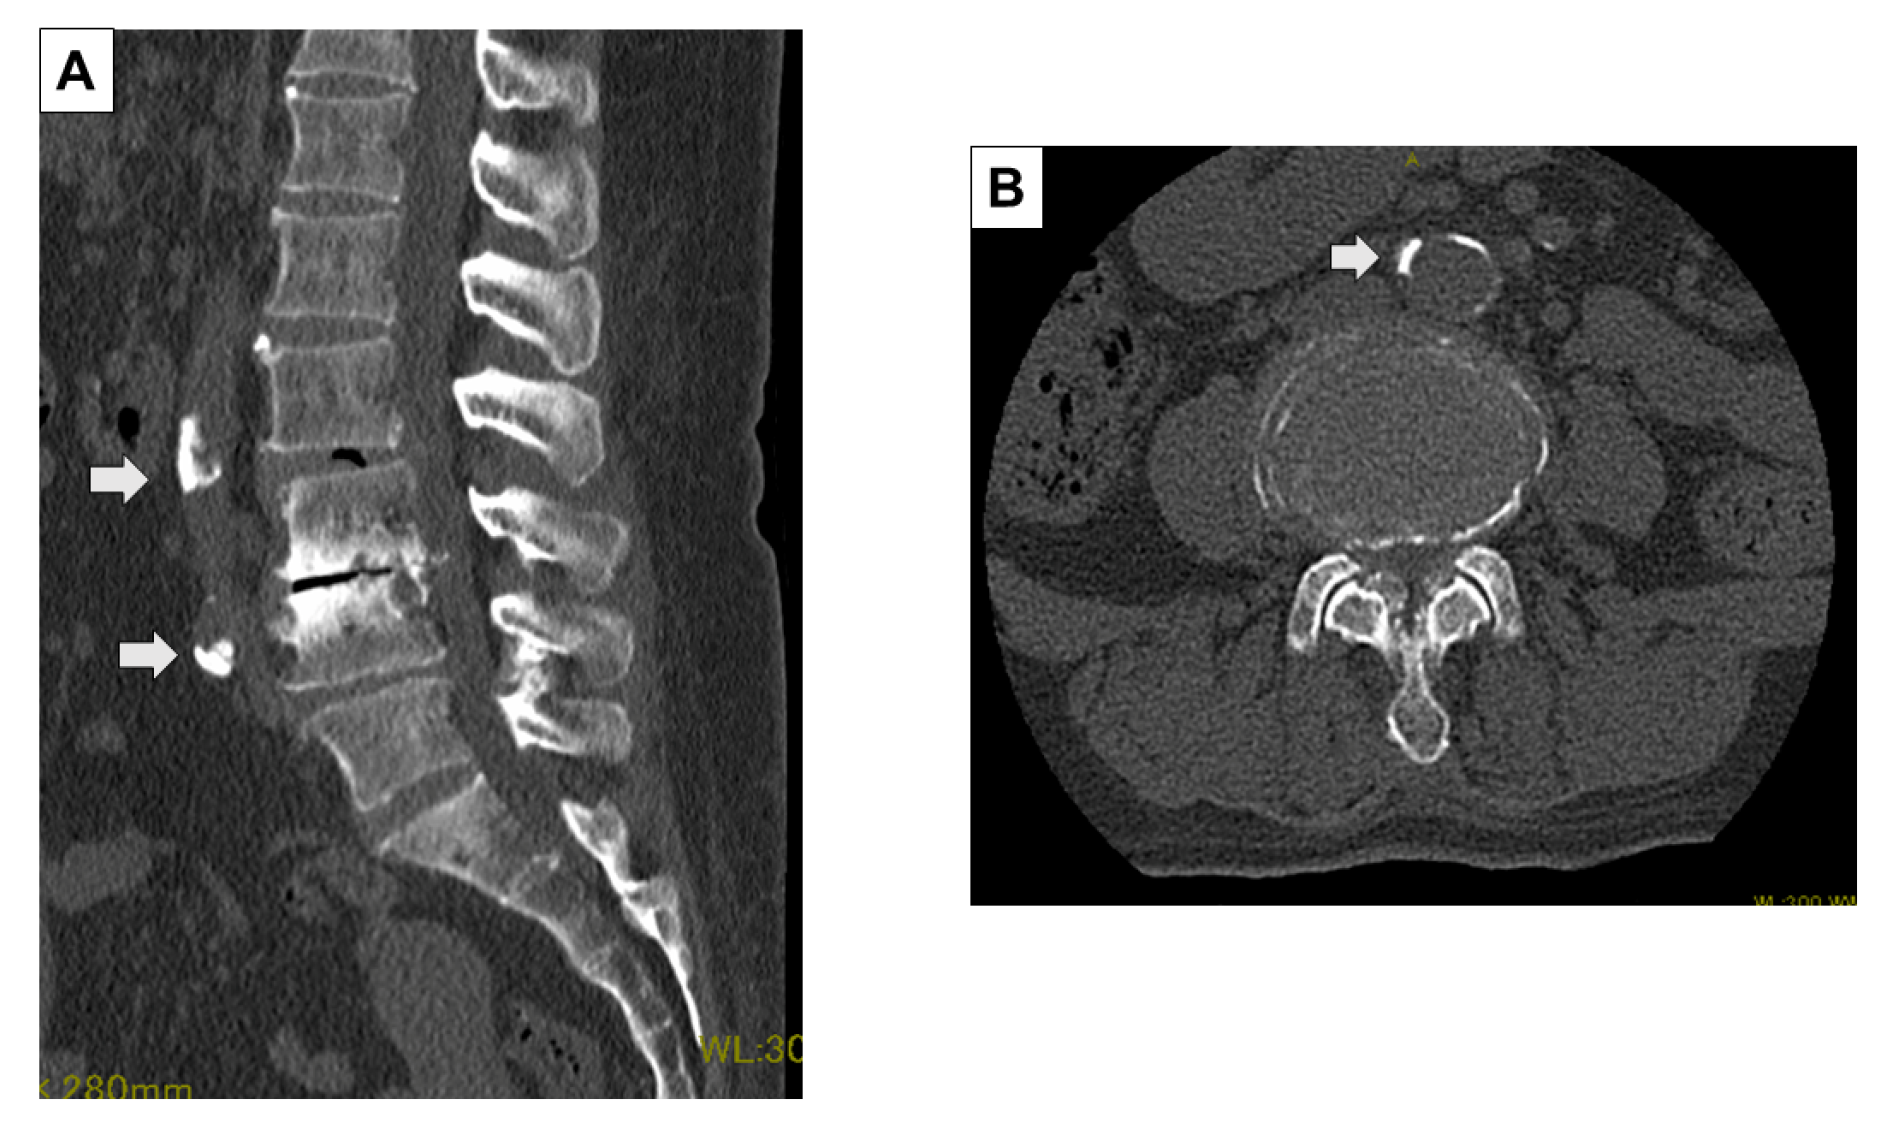

2.2. Evaluation Method of Preoperative and Intraoperative CT Images